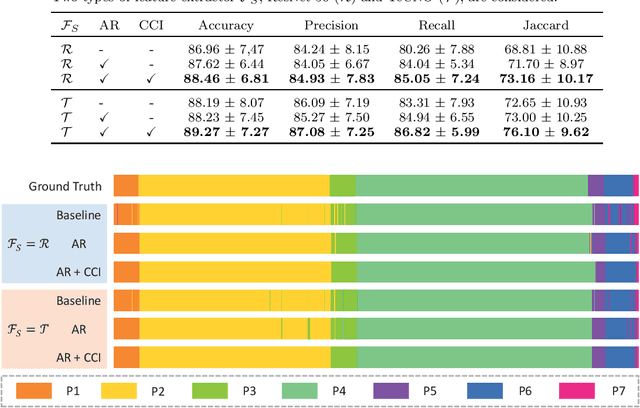

ARST: Auto-Regressive Surgical Transformer for Phase Recognition from Laparoscopic Videos

Sep 02, 2022

Abstract:Phase recognition plays an essential role for surgical workflow analysis in computer assisted intervention. Transformer, originally proposed for sequential data modeling in natural language processing, has been successfully applied to surgical phase recognition. Existing works based on transformer mainly focus on modeling attention dependency, without introducing auto-regression. In this work, an Auto-Regressive Surgical Transformer, referred as ARST, is first proposed for on-line surgical phase recognition from laparoscopic videos, modeling the inter-phase correlation implicitly by conditional probability distribution. To reduce inference bias and to enhance phase consistency, we further develop a consistency constraint inference strategy based on auto-regression. We conduct comprehensive validations on a well-known public dataset Cholec80. Experimental results show that our method outperforms the state-of-the-art methods both quantitatively and qualitatively, and achieves an inference rate of 66 frames per second (fps).